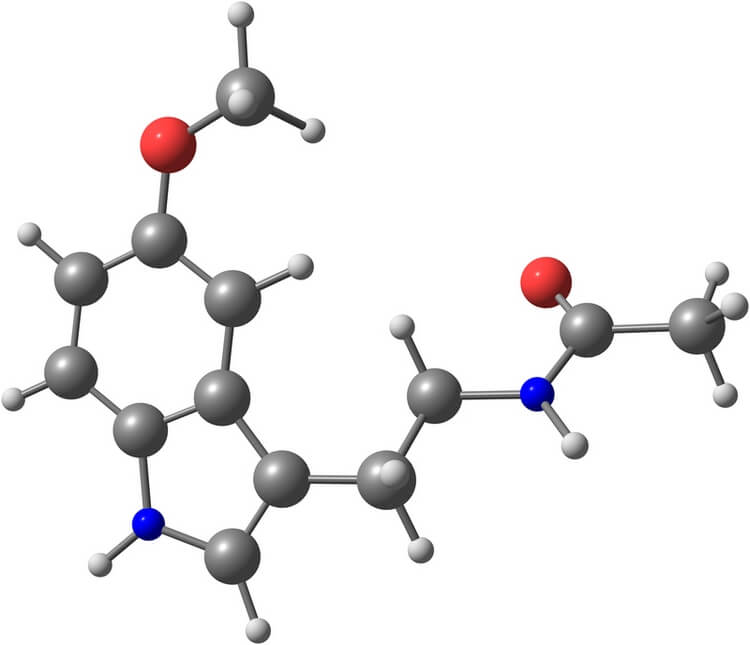

Многие люди уже слышали про гормон сна – мелатонин. Также его называют гормоном жизни или долголетия. Ученые до сих пор изучают свойства этого вещества, но положительное воздействие его на организм человека и его необходимость для нормальной жизнедеятельности уже установлены.

Рассматривая вопрос о том, как вырабатывается мелатонин, чаще всего связывают его производство с эпифизом или шишковидной железой. Под действием солнечного света аминокислота триптофан в организме преобразуется в серотонин, который ночью уже превращается в мелатонин. После его синтеза в эпифизе мелатонин попадает в спинномозговую жидкость и кровь. Таким образом, для всех этих преобразований необходимо ежедневно по полчаса-часу проводить на улице в светлое время суток.

Гормон мелатонин вырабатывается в организме при разнообразном питании, которое обязательно должно содержать углеводы, белки, кальций и витамин В6. В некоторых продуктах питания мелатонин содержится в чистом виде, в других – необходимые для его синтеза компоненты.